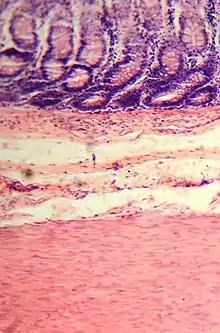

Histología del intestino grueso

Presenta criptas de Lieberkühn, no tiene vellosidades ni pliegues circulares.[44] Presenta, en la túnica serosa, evaginaciones. Una evaginación llena de tejido adiposo constituye un apéndice omental.

En el intestino grueso hay una gran cantidad de exocrinocitos caliciformes. Las poblaciones celulares epiteliales son las mismas del intestino delgado.[45][46]